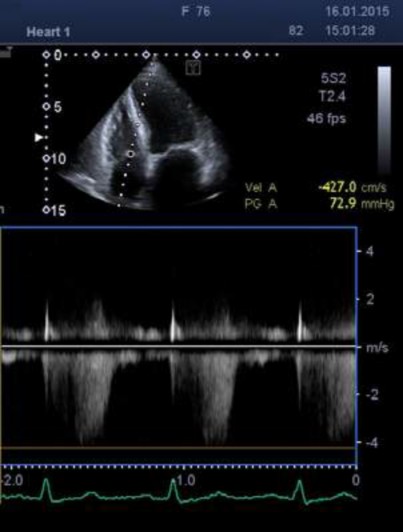

Mitral Valve Stenosis - Echocardiography, Diagnosis, Causes, Severity

ecgwaves.com

ecgwaves.com

mitral regurgitation stenosis echocardiography chordae tendineae echo ecg anterior papillary medial rupture scallops scallop ekg ecgwaves congenital riss